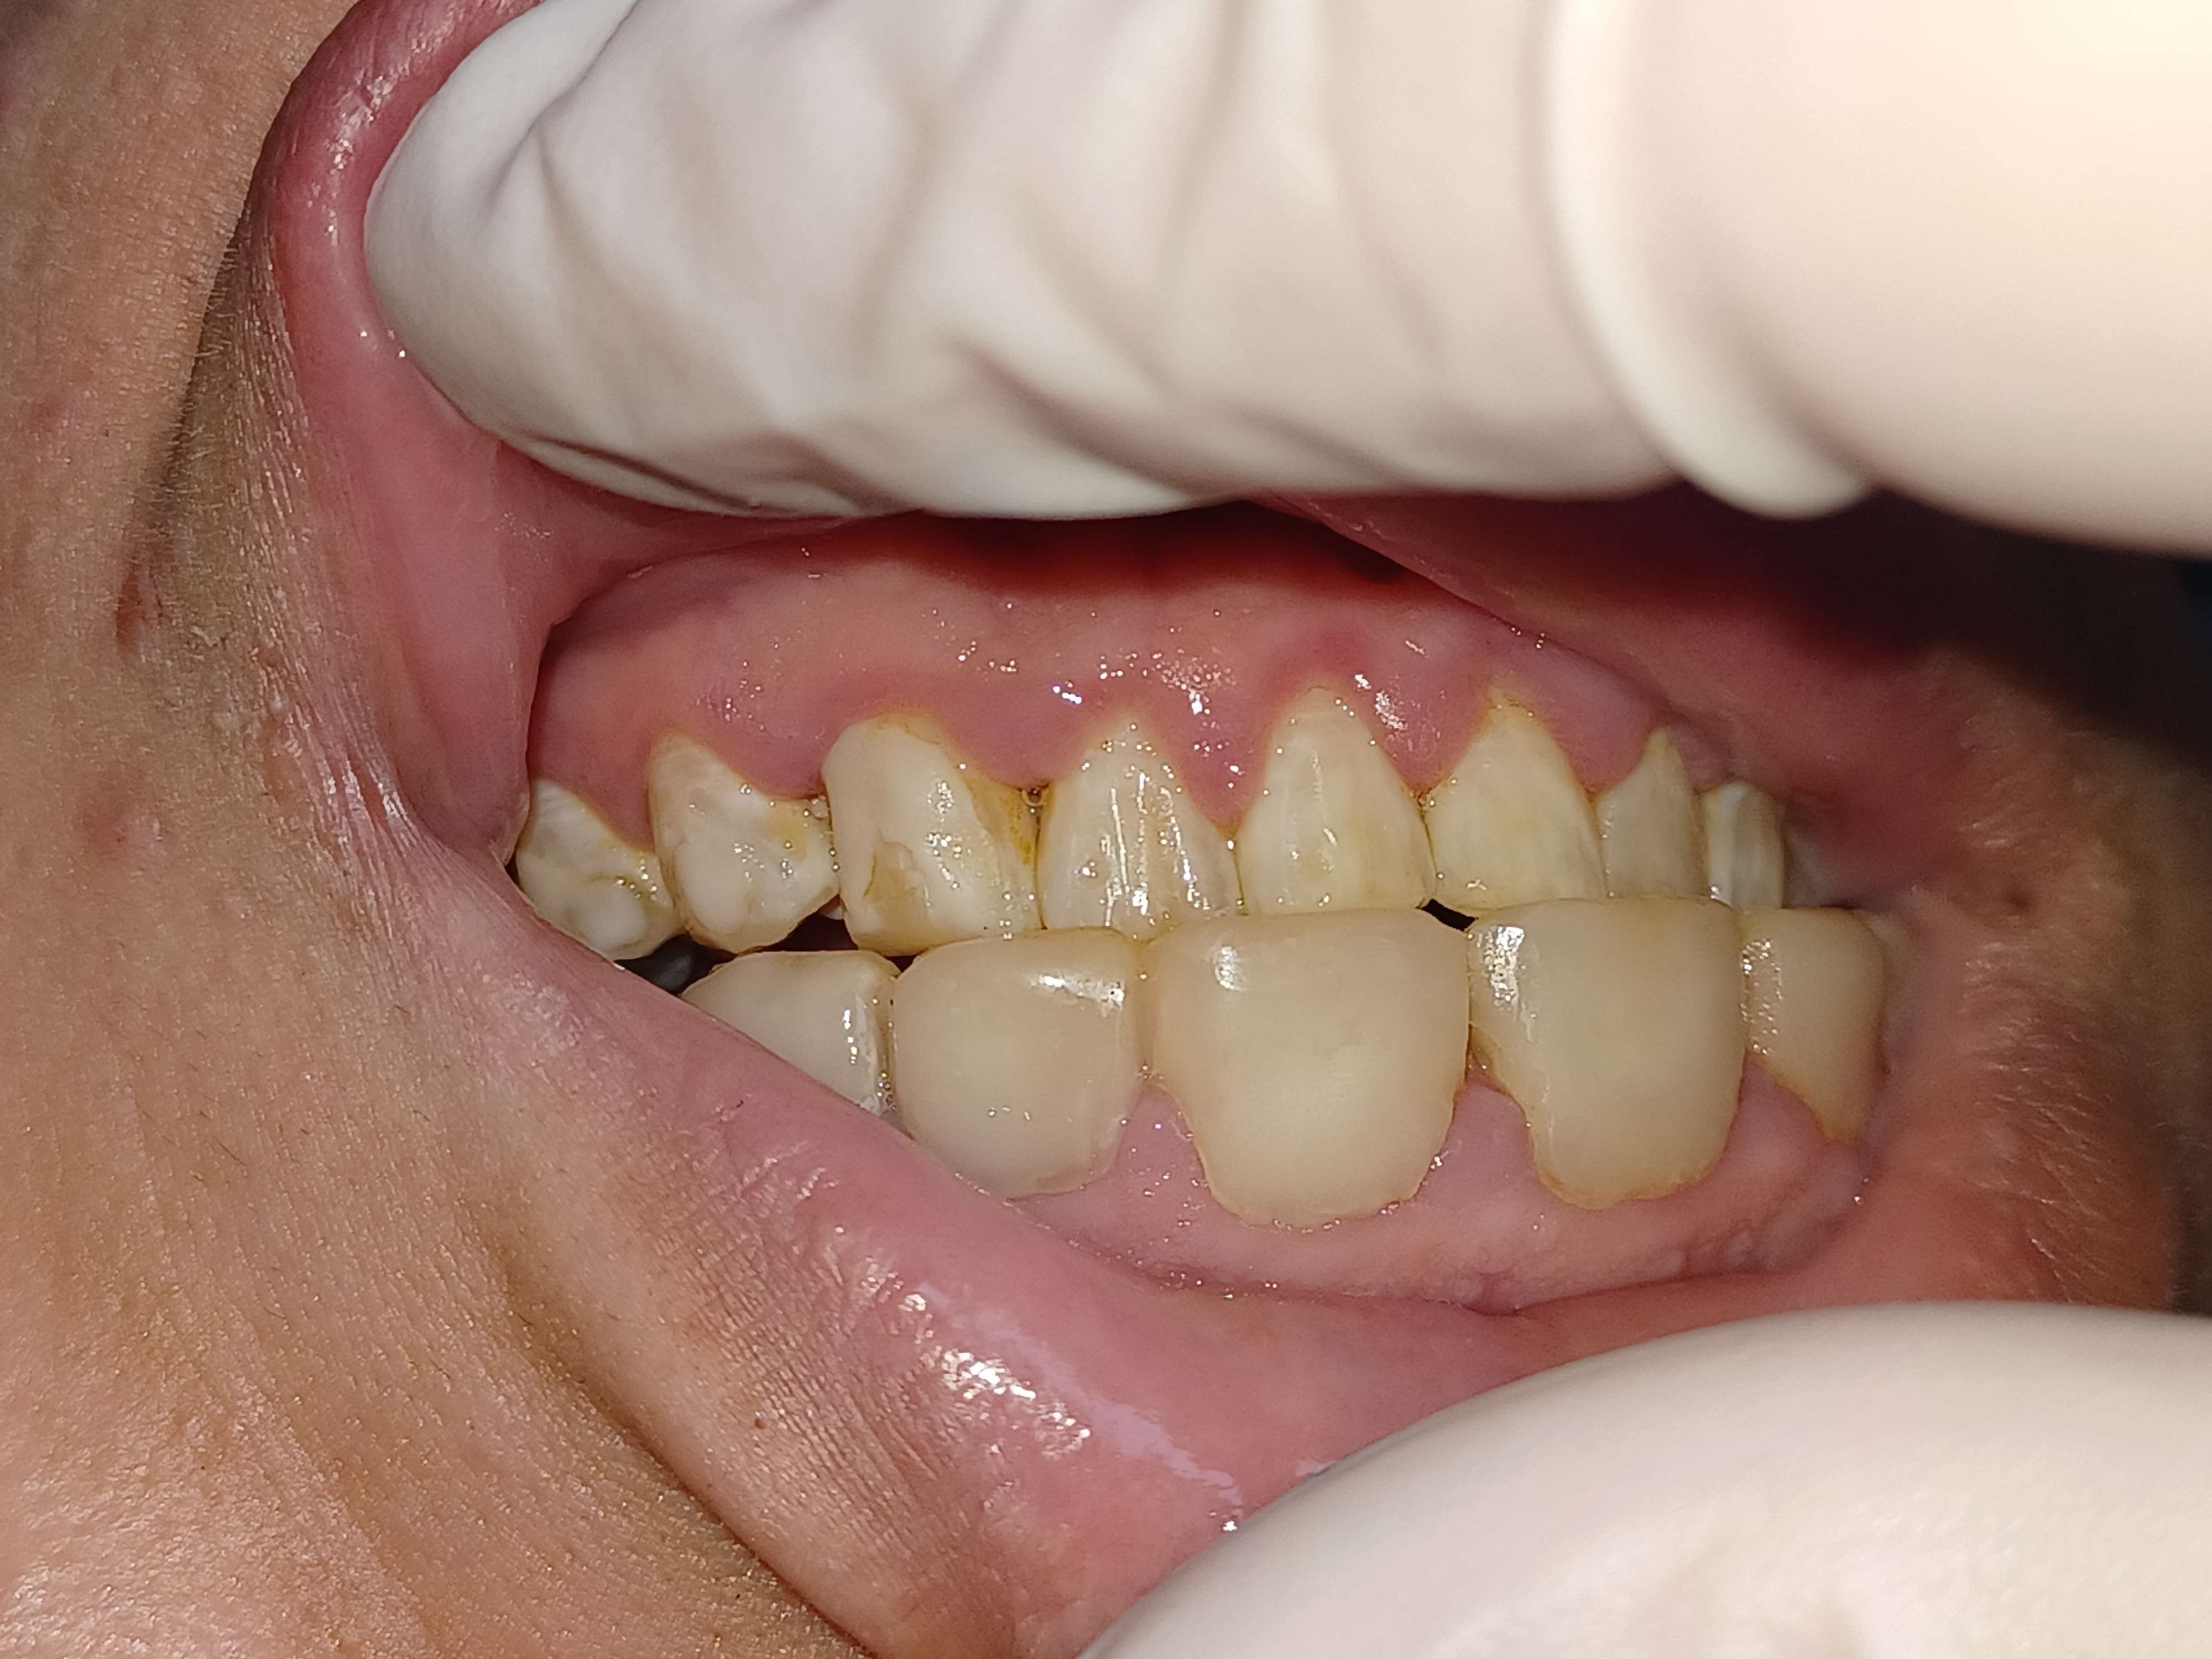

N'y aurait il pas avant tout un pb d'hygiène de la patiente, et en second lieu cela ressemble à des composites.

Elle est mécontente de son praticien précédent, mais est-elle contente de son hygiène de chacal?

Je vais me faire l'avocat du diable mais au vu de l'état général de ses dents et de son parodonte sur la pano, son hygiène buccale ne semble pas si pourrie.

Oui enfin, y'a pas un espace interdentaire sans inflammation, en haut comme en bas, même là ou les compos ne sont pas juxta sulcus. Toutes les papilles sont inflammatoires. Donc c'est sûr que faire des facettes, en plus à l'arrache sur ce genre de cas ça ne peut pas donner un joli résultat.

Franchement, elle a peut être bien brossé avant le RDV mais il n'y a quasiment pas de plaque, et l'inflammation est limitée. Pour moi c'est 90% iatrogène, améliorer l'hygiène n'y changera pas grand chose.

Gabzou, Olieve, vous rigolez ou quoi ? à la mandibule où il n'y a pas de facettes compo toutes les papilles sont œdématiées, et encore plus qu'au maxillaire ! une bonne gingivite du bloc inf. Donc OK pour le iatrogène en plus, mais y'a un problème d'hygiène à la base.